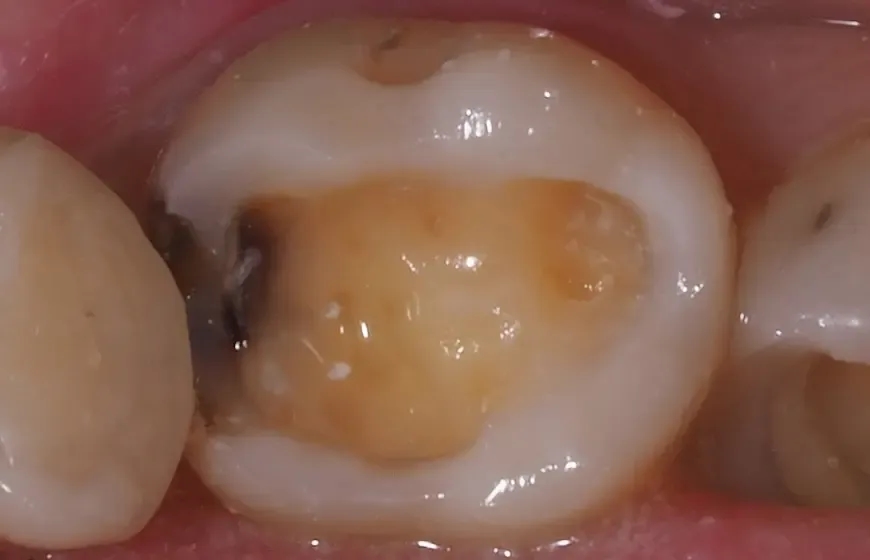

W przypadku problemów z zębami, istnieje wiele objawów, które powinny skłonić do wizyty u dentysty. Najczęściej występującym symptomem jest ból zęba, który może być ostry lub tępy, a także stały lub pojawiający się sporadycznie. Inne objawy to nadwrażliwość na gorące lub zimne napoje, co może wskazywać na uszkodzenie szkliwa lub zębiny. Widoczne uszkodzenia zęba, takie jak przebarwienia czy widoczne ubytki, również są sygnałem, że należy skonsultować się z dentystą.

- Widoczne ubytki – jakiekolwiek uszkodzenia lub przebarwienia na zębach.

Gdy ubytek w zębie jest zbyt duży, aby mógł się samodzielnie zagoić, dostępne są różne metody leczenia. Najczęściej stosowaną metodą jest plombowanie, które polega na wypełnieniu ubytku materiałem kompozytowym lub amalgamatem. W przypadku bardziej zaawansowanych uszkodzeń, konieczne może być zastosowanie korony, która pokrywa cały ząb, przywracając mu funkcję i estetykę. W skrajnych przypadkach, gdy ząb jest poważnie uszkodzony, może być konieczne przeprowadzenie leczenia kanałowego, które polega na usunięciu miazgi zęba i wypełnieniu kanałów korzeniowych odpowiednim materiałem.